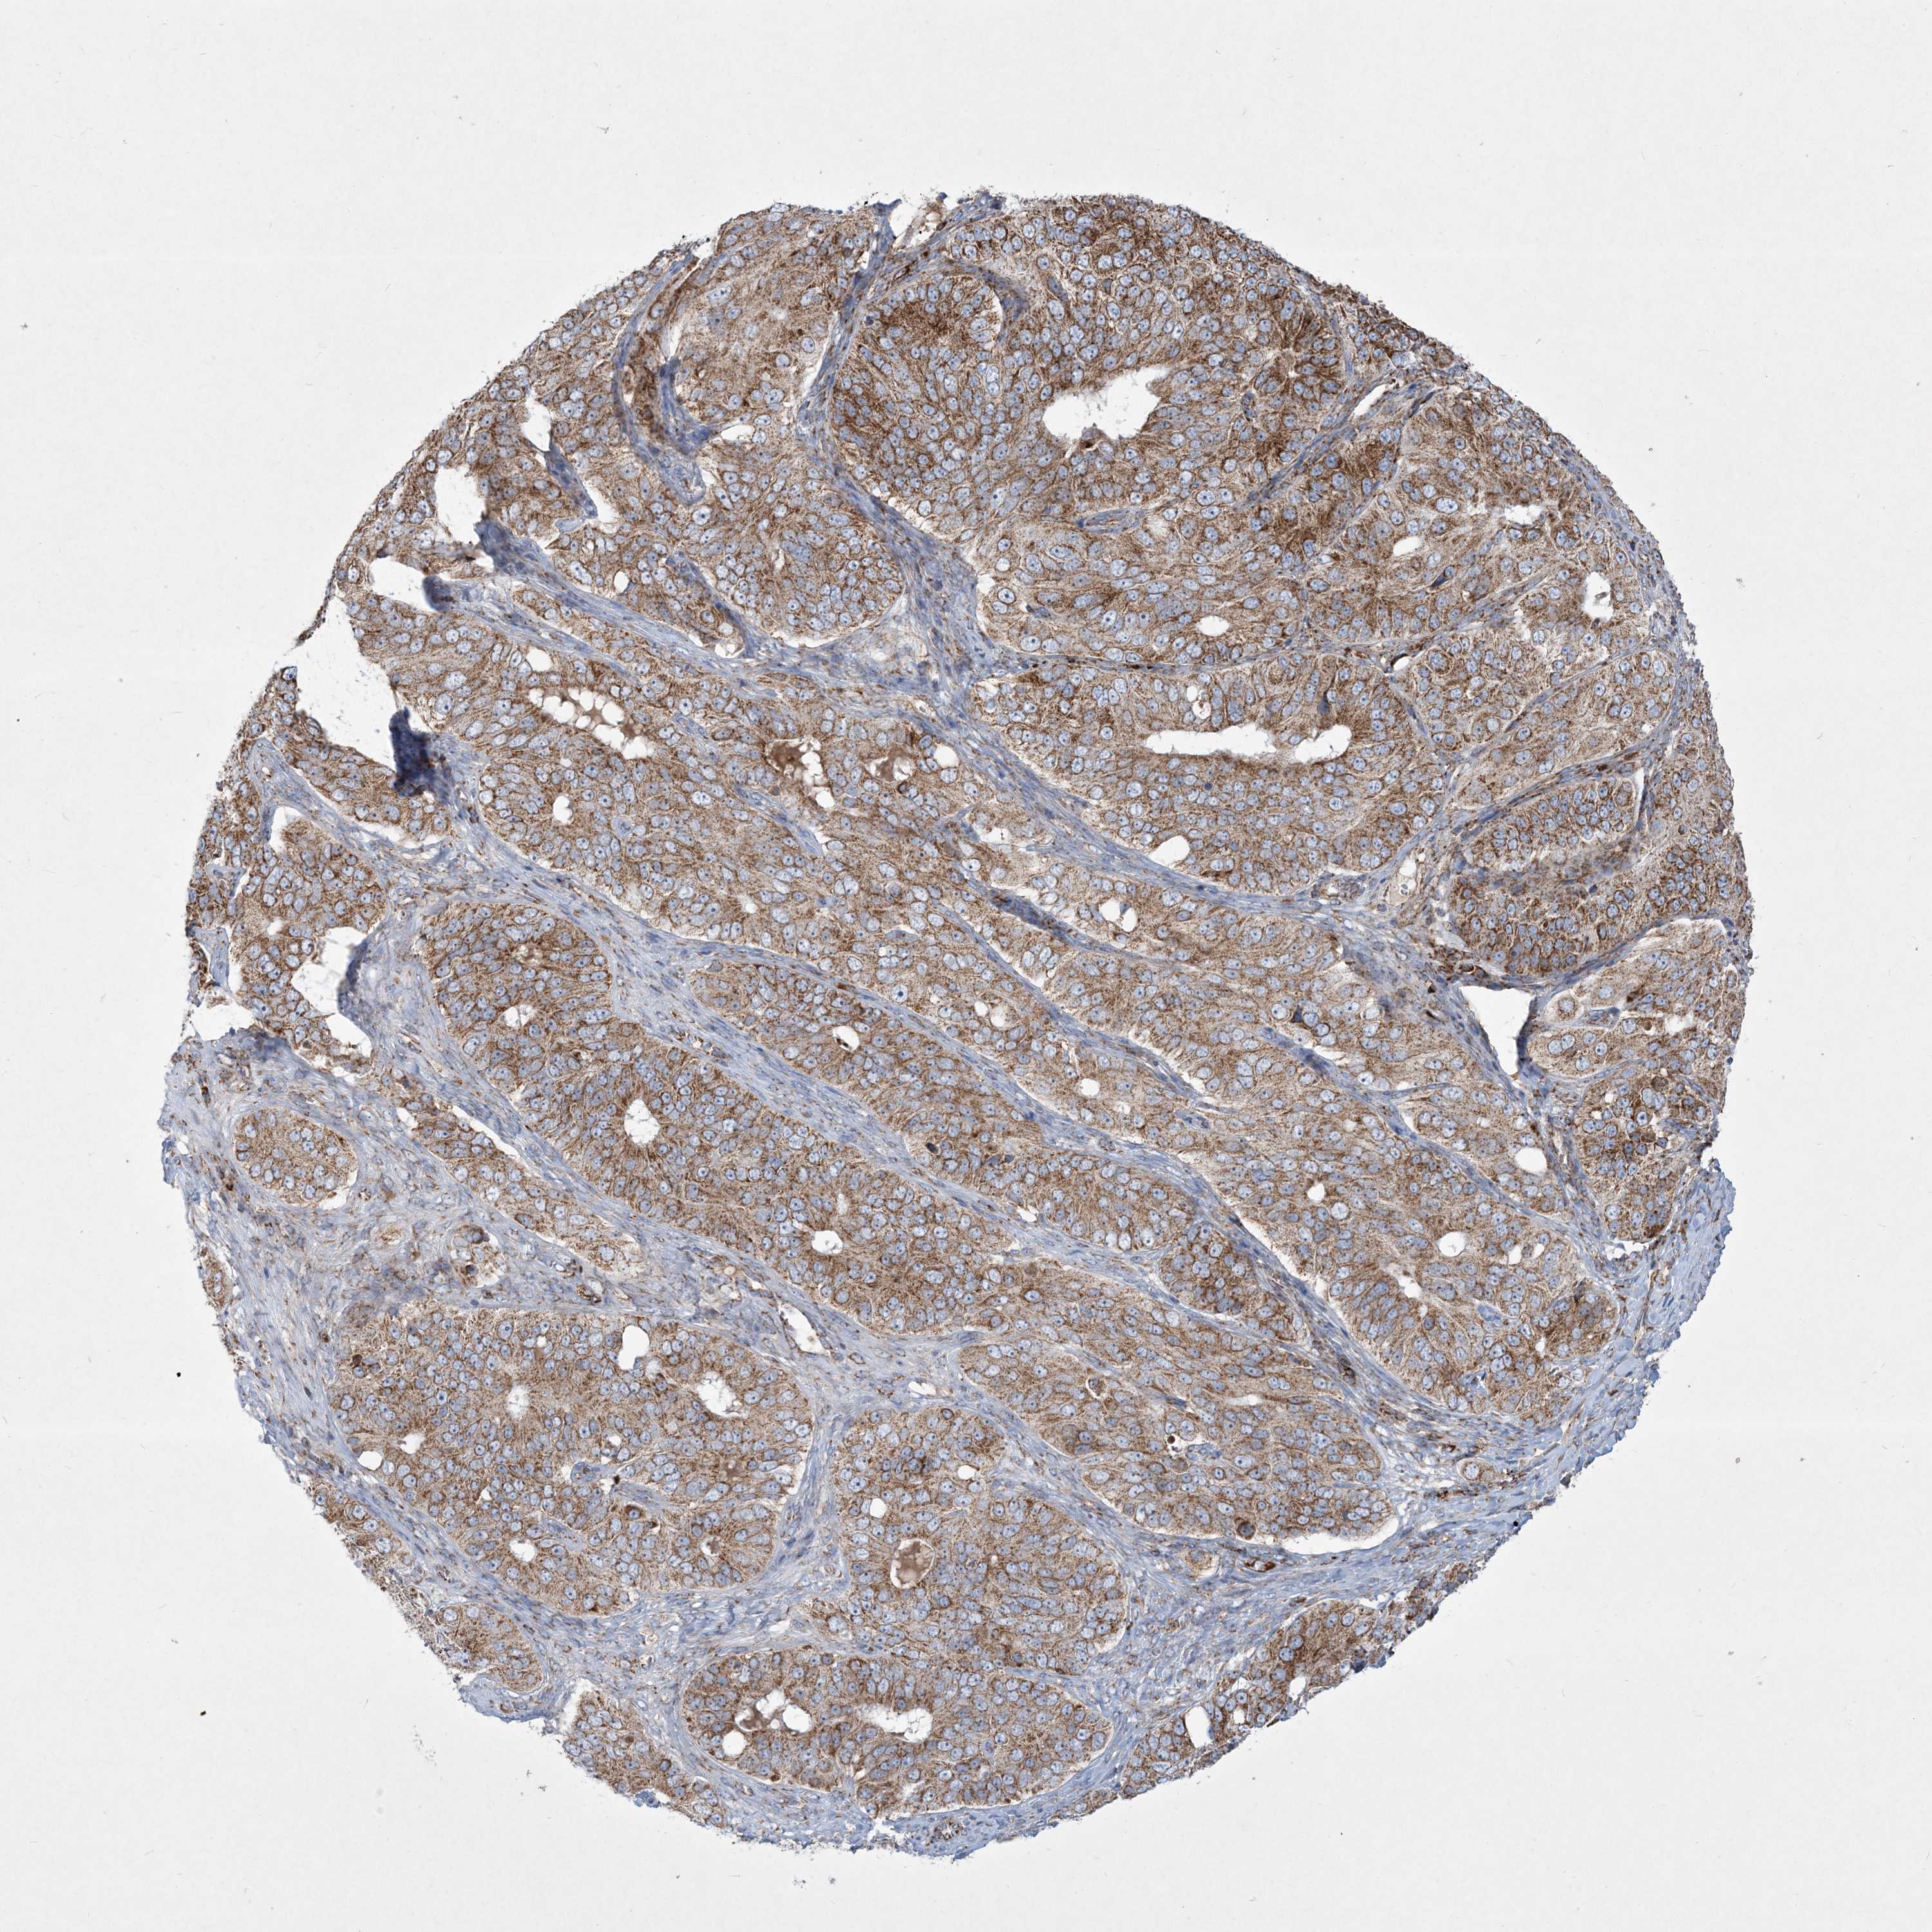

OVARIAN CANCER - Protein expressioni

A mouse-over function shows sample information and annotation data. Click on an image to view it in a full screen mode. Samples can be filtered based on level of antibody staining by selecting one or several of the following categories: high, medium, low and not detected. The assay and annotation is described here.

Note that samples used for immunohistochemistry by the Human Protein Atlas do not correspond to samples in the TCGA dataset.

Antibody stainingi

Antibody staining in the annotated cell types in the current human tissue is reported as not detected, low, medium, or high, based on conventional immunohistochemistry profiling in selected tissues. This score is based on the combination of the staining intensity and fraction of stained cells.

Each image is clickable and will lead to virtual microscopy that enables deeper exploration of all samples and also displays staining intensity scores, fraction scores and subcellular localization as well as patient and tissue information for each sample.

Antibody HPA036850

Staining

High

Medium

Low

Not detected

Intensity

Strong

Moderate

Weak

Negative

Quantity

>75%

75%-25%

<25%

None

Location

Nuclear

Cytoplasmic/membranous

Cytoplasmic/membranous,nuclear

Cystadenocarcinoma, serous, NOS

Carcinoma, endometroid

Cystadenocarcinoma, mucinous, NOS

Carcinoma, NOS